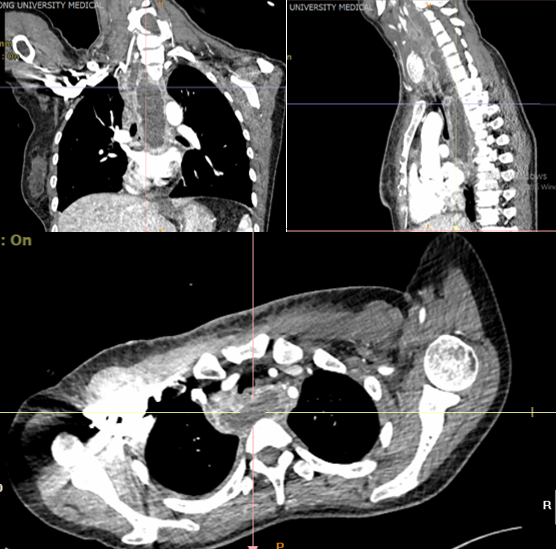

胸外科李少民主任评估患者病情后与家属沟通:“患者目前诊断为纵脓肿,已出现感染性休克表现,病情危重,药物保守治疗好转机会渺茫,需进行手术探查,但手术风险极大;但我们一定会尽最大努力为患者争取一线生机。”家属同意手术治疗。在准备急诊手术的过程中,同时给予抗休克治疗,并急诊完成了胃镜、电子支气管镜、增强CT等检查;评估患者纵隔脓肿是否由食管或气管损伤引起,进一步明确脓肿与周围组织及血管的解剖关系。术前准备完善后,第一时间接入急诊手术间进行手术。因脓肿波及颈部、胸部,且颈部肿胀严重、气管受压,全麻气管插管也是一个挑战;幸运的是由经验丰富的麻醉医师张鹏顺利完成了气管插管。此时面临更大的挑战:手术入路的选择是颈部入路还是胸部入路?能否通过一个入路解决问题?李少民主任通过详细阅读术前检查以及丰富的临床经验选择行颈部左侧切开,于胸锁乳突肌深面暴露脓肿,探查脓肿位于椎前间隙,上达会厌后方,下至后纵隔气管分叉,有大量黄色浑浊脓液积存,吸出脓液,量约150ml;过氧化氢液冲洗,于颈部切口沿椎前间隙留置负压引流管两根,上管至会厌上方,下管至气管分叉水平,引流满意。术后给予抗感染及支持疗法,术后第1天患者颈部肿胀明显好转,呼吸困难及声音嘶哑明显好转,体温正常。患者清楚的向医生说出“谢谢您们把我从鬼门关拉了回来。”